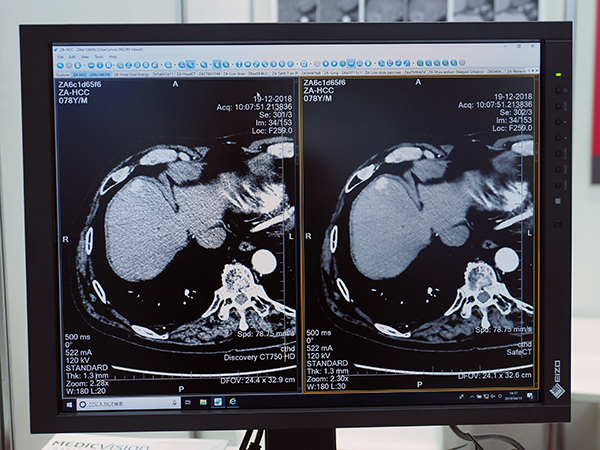

長瀬産業が主力製品として販売に力を入れているのが,イスラエルのMedic Vision Imaging Solutionsが開発した逐次近似画像再構成ソフトウエア“SafeCT”である。イスラエルは,GEやシーメンス,フィリップスなどのモダリティメーカーの研究施設が多くあり,そこで働いていたエキスパートたちが独立し,2006年に設立したのが,Medic Vision Imaging Solutionsである。そして,彼らがモダリティメーカーで学んだ技術やノウハウを土台として,開発したのがSafeCTだ。SafeCTは,CT画像のノイズを低減する逐次近似画像再構成処理を画像ベースで行うソフトウエアである。逐次近似画像再構成技術を搭載していないCTでも,低線量での検査を可能にする。撮影したCT画像から演算処理を行い,ノイズを除去しつつ,従来の逐次近似画像再構成法の画像で問題となっていた違和感のない画質を実現している。設定できる部位または領域は,頭部,胸部・肺,腹部・骨盤,脊椎,整形外科で,sharp,default, soft+,soft++,soft+++の5段階の調整が可能である。

米国では2011年にFDAの承認を受けてその後販売が開始され,すでに250施設を超える稼働実績がある。日本国内では,2018年から販売を開始。導入施設はまだ多くないものの,導入施設はもとより,現在評価を行っている施設からも多くの反響があるという。長瀬産業としては,当初逐次近似画像再構成技術を搭載していないCTを使用している施設をターゲットとしていたが,いざ国内販売を開始してみると,逐次近似画像再構成技術を搭載したCT導入施設からも高評価を得ているそうだ。これは,装置に搭載された逐次近似画像再構成技術で生成したデータを,さらにSafeCTで処理することにより,より読影しやすい,自然なテクスチャを持った画像にできるためである。実際の運用としては,まずCT搭載の逐次近似画像再構成技術を用いて金属アーチファクトの低減処理などを行った上で,SafeCTで画質の改善を図るといったことが行われている。なお,SafeCTは,原理的にコーンビームCT画像にも適用可能であり,同社としても今後検証を行っていくこととしている。

ノイズを大幅に低減して被ばく低減に寄与する“SafeCT”(右)

従来の逐次近似画像再構成技術と一線を画し「低線量画像革命」をうたう“SafeCT”